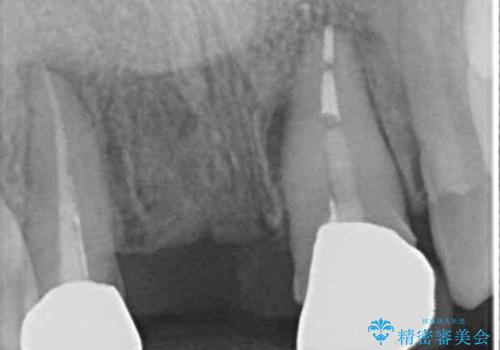

- 矯正治療中に装着していた仮歯を綺麗にしたいとのことで来院された患者様です。

小学生の頃に歯をぶつけて抜歯となりブリッジを装着したそうですが、その後矯正治療を行うに当たりブリッジを切断したとのことでした。

残っている歯根の状態はあまり良くなく、長期的な予後を考えると抜歯を検討するべきでしたが、20代前半という年齢を考え、オールセラミックブリッジにて補綴治療を行うこととしました。